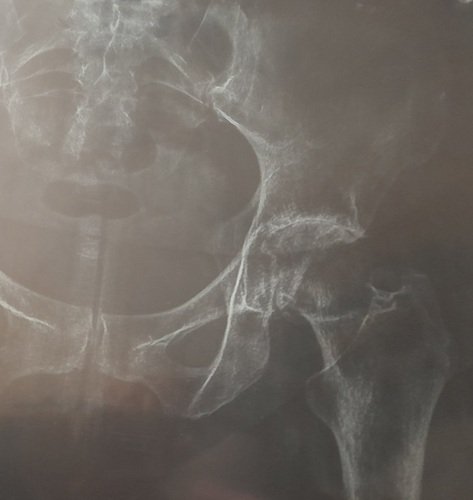

Olá me chamo Aline ,estou passando por uma fase muito difícil pois venho fazendo vários exames e acompanhamento médico.Estou com um problema muito sério de cartilagem que por conta disso terei que realizar uma cirugia no quadril .E devido o valor ser muito alto ,venho caricidamente pedir ajuda de todos que poderem ,pois o valor dessa cirurgia e 85.000,00 .Eu estou na fila do SUS ,só que o retorno e quase impossível pela minha idade, sinto muita dor e por isso não ando sem a muleta ,e fora os remédios fortes que estou tomando devido a dor.Desde de já agradeço a cada um de vocês que Deus abençoe.